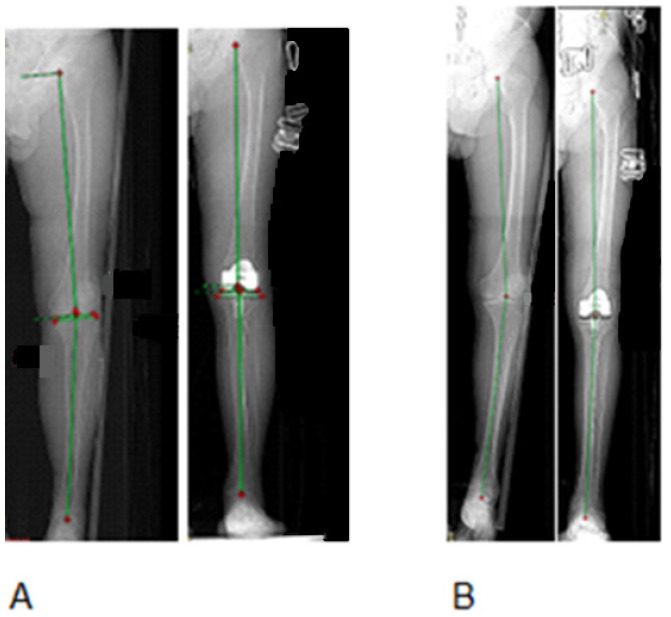

Background: Lower limb malalignment is a hallmark of knee osteoarthritis, with surgical correction techniques evolving from traditional mechanical alignment (MA) to kinematic alignment (KA) approaches. Restrictive kinematic alignment (rKA) represents a hybrid strategy combining principles from both techniques. This study evaluated short-term functional outcomes following robotic-assisted total knee arthroplasty (RoTKA), comparing MA versus rKA alignment strategies. Methods: This prospective, randomized, single-center study enrolled 96 patients with grade 3-4 idiopathic knee osteoarthritis (Kellgren-Lawrence classification). Patients were randomized to MA (n = 49, mean age 67 ± 9 years) or rKA (n = 47, mean age 66 ± 7 years) groups. Preoperative hip-knee-ankle (HKA) angles were 172.6° ± 1.1° and 172.9° ± 0.9° for MA and rKA groups, respectively. Outcomes were assessed using Visual Analog Scale (VAS) pain scores, range of motion (ROM), Knee Society Score (KSS), Oxford Knee Score (OKS) (primary outcome), SF-36, and Forgotten Joint Score (FJS-12). Results: Postoperative HKA angles were 179.5° ± 1.2° (MA) and 176.0° ± 1.5° (rKA). At 14 days postoperatively, knee ROM increased by 20.5% in the MA group and 25.7% in the rKA group, with a statistically significant 5.2% intergroup difference, indicating faster postoperative recovery (p = 0.008). VAS pain scores decreased by 7% in the rKA group while increasing by 13% in the MA group (p < 0.001). At one-year follow-up, FJS-12 scores were significantly higher in the rKA group (94.8 ± 3.2 vs. 91.9 ± 2.2, p < 0.001). No significant differences were observed in KSS, OKS, or SF-36 score between groups. Conclusions: Restrictive kinematic alignment demonstrated superior early postoperative outcomes compared to mechanical alignment in RoTKA, with significantly reduced pain and improved ROM. While one-year functional outcomes were comparable between techniques, rKA may offer advantages in the immediate postoperative period, supporting its consideration as a viable alignment strategy in robotic-assisted knee arthroplasty.